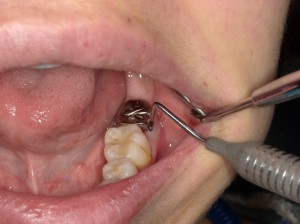

普通に抜くだけでも緊張です

歯医者ならば嫌な予感しかしないですよね。歯冠が深めで・・・

頑張って抜歯し、速攻で移植!

へーベルかけたところは縁上になるように移植

骨縁下に仮蓋が・・・